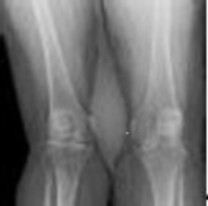

4. # 23a 23b A 15-year-old girl is referred to your office by her primary care physician who is concerned about a "shadow on the bone" noted when office radiographs were obtained following a minor soccer accident. The patient denies any history of knee pain, and has been fully active without any restrictions. Examination is consistent with a minor sprain but otherwise is unremarkable. The lesion is shown in Figures 23a and 23b. What is the most likely diagnosis?

DISCUSSION: The AP and lateral radiographs reveal a lytic, eccentric, well-marginated (mildly sclerotic) lesion that is minimally expansile of the cortex (on the lateral image). This is the classic appearance of a nonossifying fibroma, which most commonly appears

in the metaphyseal region of the lower extremity long bones, particularly around the knee, and in a young patient population. The lesion may also have a "bubbly" appearance, which is not demonstrated in this particular case. Unless the lesion is large, or accompanied by a pathologic fracture, they are generally incidental findings, as in this patient. Giant cell tumor is a more destructive lesion that is typically subchondral in location generally in somewhat older patients. Osteofibrous dysplasia, which may have a somewhat similar appearance, is almost always diaphyseal in location and typically involves the anterior cortex. Enchondroma is not typically eccentric, and while it may have a lytic appearance, usually demonstrates mineral density in the lesion, and is not generally sclerotic at the margin. Infection may have an extremely variable radiographic appearance, but would typically appear more aggressive and present with underlying symptoms. The Preferred Response to Question # 23 is 1.